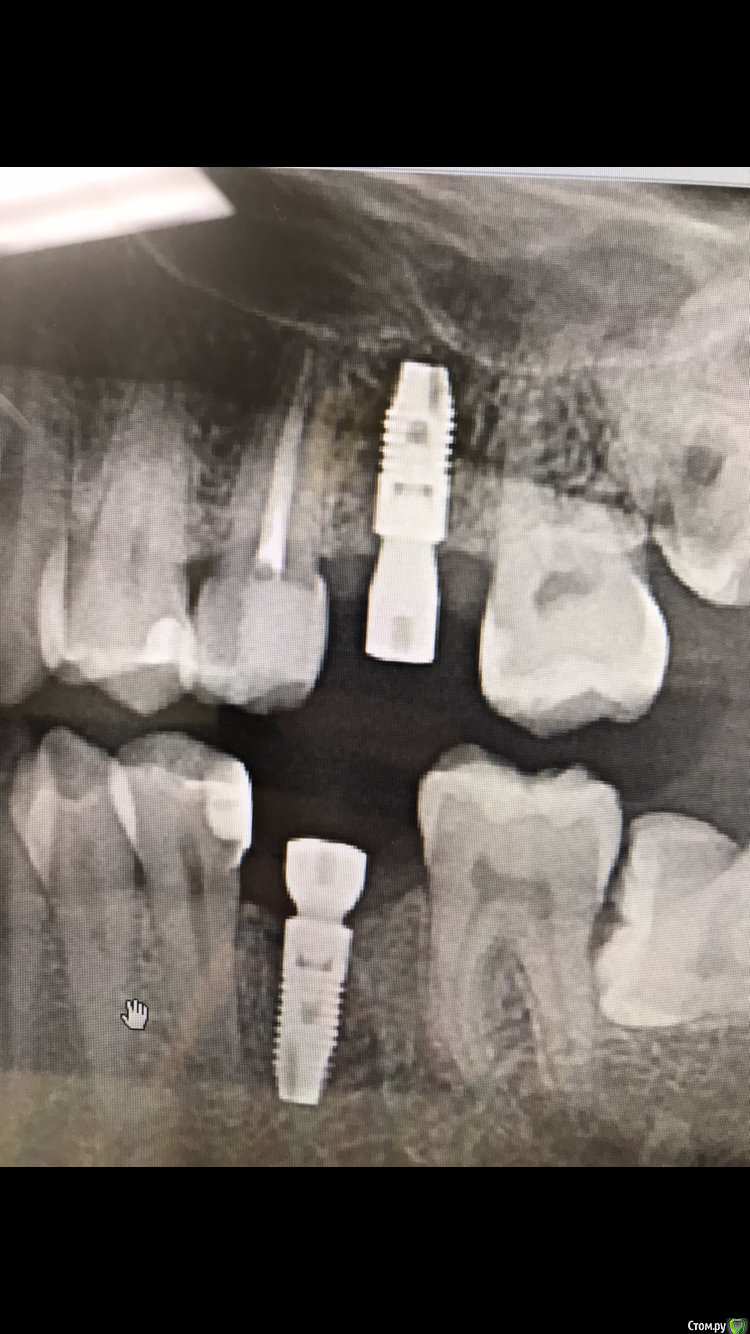

El_cucuy Опубликовано 22 января, 2020 Поделиться Опубликовано 22 января, 2020 (изменено) 1) поставить низкую заглушку, подшить сверху трансплантат под лоскутки 2) не делать ничего до интеграции, решать вопросы на втором этапе Доброго времени суток , доктора . По состоянию на 20 декабря , вот такая картина , нужно ли подсаживать трансплантат? Изменено 22 января, 2020 пользователем El_cucuy Ссылка на комментарий

El_cucuy Опубликовано 22 января, 2020 Поделиться Опубликовано 22 января, 2020 (изменено) нужны фото. И создавайте свои темы, а не засоряйте чужиеТот же кейс , добавил спустя 2 месяца Изменено 22 января, 2020 пользователем El_cucuy Ссылка на комментарий

Дмитрий Л. Опубликовано 26 января, 2020 Поделиться Опубликовано 26 января, 2020 Я бы не подсаживал, вроде 3 мм есть. 1 Ссылка на комментарий

red_butler Опубликовано 26 января, 2020 Поделиться Опубликовано 26 января, 2020 не вижу смысла работать с десной Ссылка на комментарий